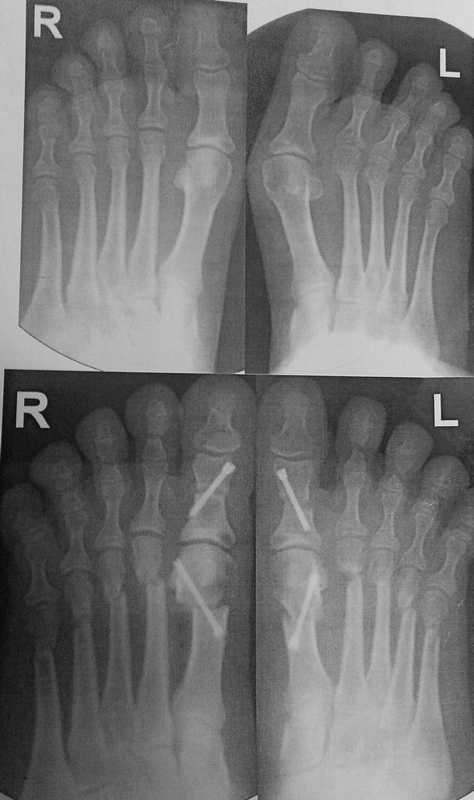

Уважаемые коллеги, я понимаю, что уже утомил вас оперированными стопами,

но помогите еще с одним случаем

Женщина около 50, активная, оперирована 1 год назад. Тип остеотомии в

выписке не указан (похоже с 1-го по 5-ую + фаланги). Сожалею. что фото

стопы не удалось выложить, клинически - выраженная девиация всех пальцев

стопы слева. Что предпринять? Латеральный релиз, утягивание (лучшего

синонима не нашел) медиальной капсулы+остеотомии 4-5 с нормальной

повязкой? 1-ый луч - SERI (для жесткости остальных- к нему притянуть),

но, головка и так скомпрометирована (или это не брать в расчет?)+

освежение ложняков+ коррегирующая остеотомия 4-5 Weil с фиксацией винтом

(или без фиксации?). С фалангами что делать? Кажется,

что ничего?